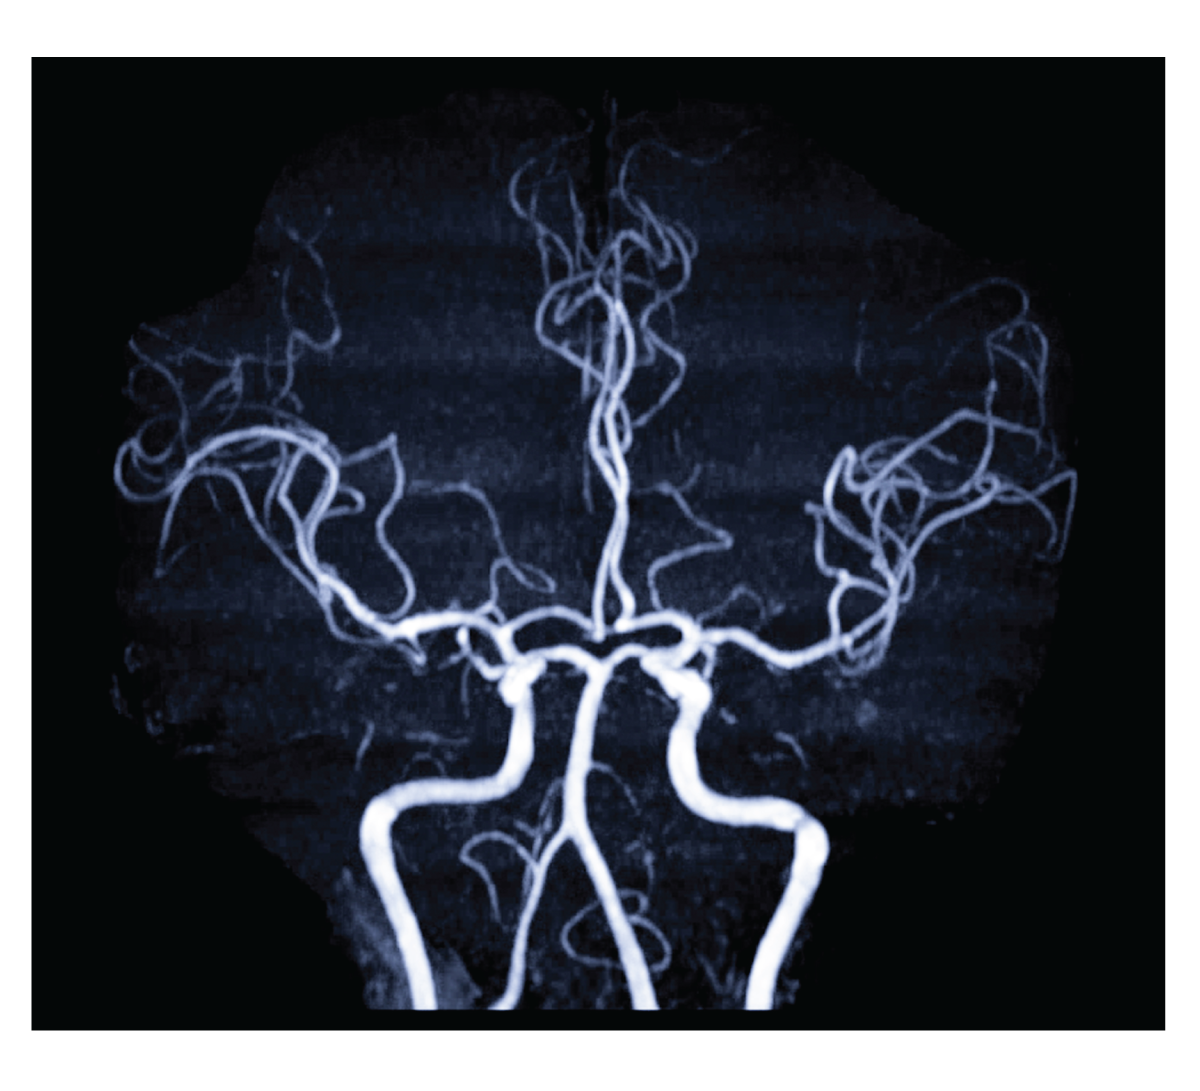

MRA Brain เทคนิค Time-of-Flight (TOF)- เทคนิคในการตรวจหลอดสมองเลือดด้วยคลื่นแม่เหล็กไฟฟ้าโดยไม่ต้องฉีดสารแกดโดลีเนียม ไม่เจ็บปวด สามารถเห็นภาพหลอดเลือดได้ชัดเจนในหลายระนาบและแบบ 3 มิติ

สามารถตรวจเส้นเลือดได้โดยไม่ต้องฉีดสารทึบแสง ทำให้ไม่มีความเสี่ยงจากสารทึบแสง